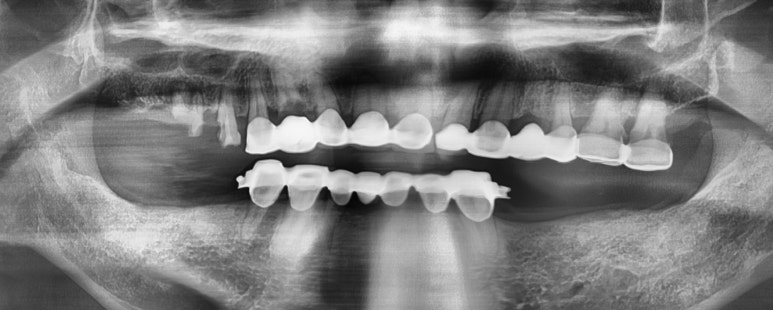

오늘은 틀니 환자분 케이스를 소개해드리려고 합니다. (포스팅 동의하셨어요)

일단 환자분 입안에는 여러가지 문제점이 있었지만

아래 틀니가 자꾸 빠져서 틀니수리할 수 있냐고 여쭤보셨습니다.

보험적용되니 새로 틀니를 저희 치과에서 건강보험적용하여 제작하기로 하셨습니다.

사실 브릿지도 야매에서 하신 거라 맘에 안들었지만

브릿지까지 다시 하면 비용이 너무 커지니 기존 야매브릿지에 맞는 형태이면서

빠지지 않게 브릿지를 활용한 부분틀니를 제작해드렸습니다.

결과적으로 요렇게 제작하셨고

이제 틀니가 안빠져서 너무 좋아하셨고요

환자분 저희 치과에서 위쪽 2개 보험임플란트도 진행하시고

충치와 시림으로 인한 신경치료 등등 다른 치료도 진행하고 계십니다.